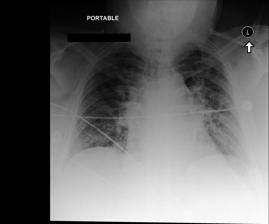

Refer to caption

Figure 1: Our conformal procedure samples candidate outputs from some blackbox LM until a stopping rule is reached. Each sample is added to the output conformal set if it meets both a minimum estimated quality and a diversity criterion. The procedure is calibrated to stop when at least one candidate y𝑦yitalic_y from the conformal set is admissible (A(y)=1)𝐴𝑦1(A(y)=1)( italic_A ( italic_y ) = 1 ) with high probability. In this example, samples y1subscript𝑦1y_{1}italic_y start_POSTSUBSCRIPT 1 end_POSTSUBSCRIPT and y2subscript𝑦2y_{2}italic_y start_POSTSUBSCRIPT 2 end_POSTSUBSCRIPT are in-admissible because they hallucinate the presence of “edema” (in orange) and “hilar congestion” (in magenta), respectively. The minimal output set includes y3subscript𝑦3y_{3}italic_y start_POSTSUBSCRIPT 3 end_POSTSUBSCRIPT, which is admissible.

To more concretely describe the exact type of guarantee that we provide, suppose we have been given a calibration set 𝒟cal=(Xi,Ai)𝒳×𝒜subscript𝒟calsubscript𝑋𝑖subscript𝐴𝑖𝒳𝒜\mathcal{D}_{\mathrm{cal}}=(X_{i},A_{i})\in\mathcal{X}\times\mathcal{A}caligraphic_D start_POSTSUBSCRIPT roman_cal end_POSTSUBSCRIPT = ( italic_X start_POSTSUBSCRIPT italic_i end_POSTSUBSCRIPT , italic_A start_POSTSUBSCRIPT italic_i end_POSTSUBSCRIPT ) ∈ caligraphic_X × caligraphic_A, i=1,,n𝑖1𝑛i=1,\ldots,nitalic_i = 1 , … , italic_n of independent and identically distributed (i.i.d.) prompts and “admission” functions (see also Fisch et al. (2021a)). Here, Aisubscript𝐴𝑖A_{i}italic_A start_POSTSUBSCRIPT italic_i end_POSTSUBSCRIPT is a binary random function that measures whether or not a generation y𝒴𝑦𝒴y\in\mathcal{Y}italic_y ∈ caligraphic_Y for prompt Xisubscript𝑋𝑖X_{i}italic_X start_POSTSUBSCRIPT italic_i end_POSTSUBSCRIPT is “good enough” (i.e., Ai(y)=1subscript𝐴𝑖𝑦1A_{i}(y)=1italic_A start_POSTSUBSCRIPT italic_i end_POSTSUBSCRIPT ( italic_y ) = 1). Note that randomness in Aisubscript𝐴𝑖A_{i}italic_A start_POSTSUBSCRIPT italic_i end_POSTSUBSCRIPT can come from implicit random covariates—such as relying on a random annotated reference, Yirefsuperscriptsubscript𝑌𝑖refY_{i}^{\mathrm{ref}}italic_Y start_POSTSUBSCRIPT italic_i end_POSTSUBSCRIPT start_POSTSUPERSCRIPT roman_ref end_POSTSUPERSCRIPT, to compare the candidate y𝑦yitalic_y to. Figure 1 illustrates a setting where Xisubscript𝑋𝑖X_{i}italic_X start_POSTSUBSCRIPT italic_i end_POSTSUBSCRIPT is an X-ray to automatically analyze and produce a report for, while Aisubscript𝐴𝑖A_{i}italic_A start_POSTSUBSCRIPT italic_i end_POSTSUBSCRIPT extracts individual findings from each generated report and checks if they correspond to those given by an expert radiologist. Let Xtestsubscript𝑋testX_{\mathrm{test}}italic_X start_POSTSUBSCRIPT roman_test end_POSTSUBSCRIPT be a new i.i.d. test prompt. Using 𝒟calsubscript𝒟cal\mathcal{D}_{\mathrm{cal}}caligraphic_D start_POSTSUBSCRIPT roman_cal end_POSTSUBSCRIPT to guide our choice of hyper-parameters λΛ𝜆Λ\lambda\in\Lambdaitalic_λ ∈ roman_Λ, for any ϵ,δ(0,1)italic-ϵ𝛿01\epsilon,\delta\in(0,1)italic_ϵ , italic_δ ∈ ( 0 , 1 ), our goal is to generate a set of samples 𝒞λ(Xtest)2𝒴subscript𝒞𝜆subscript𝑋testsuperscript2𝒴\mathcal{C}_{\mathcal{\lambda}}(X_{\mathrm{test}})\subseteq 2^{\mathcal{Y}}caligraphic_C start_POSTSUBSCRIPT italic_λ end_POSTSUBSCRIPT ( italic_X start_POSTSUBSCRIPT roman_test end_POSTSUBSCRIPT ) ⊆ 2 start_POSTSUPERSCRIPT caligraphic_Y end_POSTSUPERSCRIPT that satisfies

While Eq. (1) stipulates the existence of at least one “acceptable” generation in 𝒞λ(Xtest)subscript𝒞𝜆subscript𝑋test\mathcal{C}_{\lambda}(X_{\mathrm{test}})caligraphic_C start_POSTSUBSCRIPT italic_λ end_POSTSUBSCRIPT ( italic_X start_POSTSUBSCRIPT roman_test end_POSTSUBSCRIPT ), it does not tell us much about individual responses, y𝒞λ(Xtest)𝑦subscript𝒞𝜆subscript𝑋testy\in\mathcal{C}_{\lambda}(X_{\mathrm{test}})italic_y ∈ caligraphic_C start_POSTSUBSCRIPT italic_λ end_POSTSUBSCRIPT ( italic_X start_POSTSUBSCRIPT roman_test end_POSTSUBSCRIPT ). Additionally, longer generations are often composed of multiple statements. In our radiology setting, a report may contain multiple findings, such as “Cardiomegaly is moderate. There is mild pulmonary interstitial edema.” We futher identify a subset of confident components that would independently be categorized as being correct (given another admission function Atestcsubscriptsuperscript𝐴𝑐testA^{c}_{\mathrm{test}}italic_A start_POSTSUPERSCRIPT italic_c end_POSTSUPERSCRIPT start_POSTSUBSCRIPT roman_test end_POSTSUBSCRIPT, this time operating over generation fragments). For example, we might predict that “Cardiomegaly is moderate.” is correct, but perhaps not “There is mild pulmonary interstitial edema.” This can not only be useful in catching incorrect statements, but can also help identify independently correct parts of a larger generation, even when the overall quality of the full generation is poor. Like Eq. (1), we calibrate this process such that it gives accurate results with high probability.